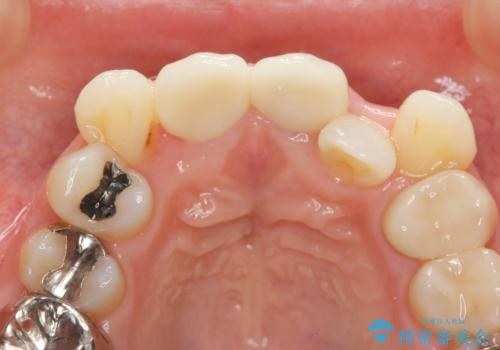

X線写真より、充填剤の突き出た状態の根管治療の再治療を行い、セラミック治療を計画すると同時に、

歯ブラシがしづらく虫歯の原因となっている歯の位置の悪い右上側切歯の抜去を行います。

- 26.4万円(ジルコニアクラウン×2・仮歯×2)費用は治療当時の料金となります

清掃を難しくしている歯を抜去することで虫歯の再発を防ぐような治療方針としました。